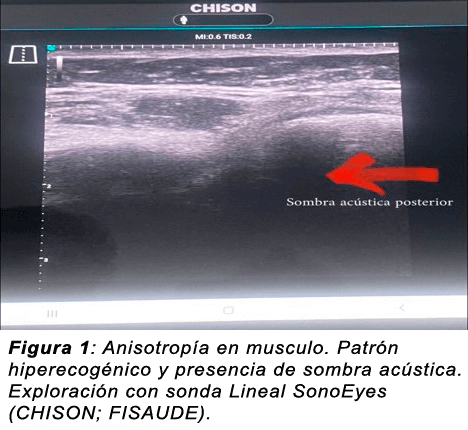

Anisotropía: A modo general se refiere al cambio de escala que se produce en una figura o cuerpo y se considera el artefacto más importante y común de la ecografía MSK. Puede aparecer a nivel del tendón y ligamentos en cortes ongitudinales y transversales. En el musculo solo se visualiza transversalmente.

Se utiliza para identificar y diferenciar un tendón de un ligamento hiperecoico (estructuras que devuelven muchos ecos en su interface, tienden a un gris muy claro casi blanco brillante).

Sombra acústica posterior: Ausencia de señal posterior por un elemento de alta intensidad. Ejemplo: el aire, el hueso y las calcificaciones.